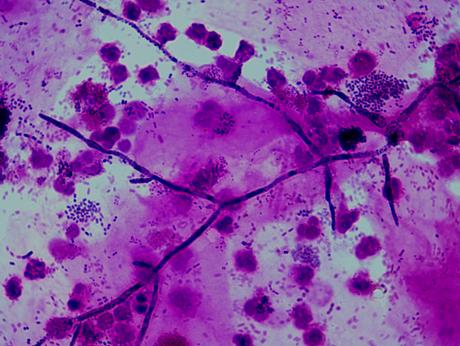

Fig. 21.5.5.5 Neisseria gonorrhoeae (coloratie Gram, x1000, imagine din colectia proprie a laboratorului)